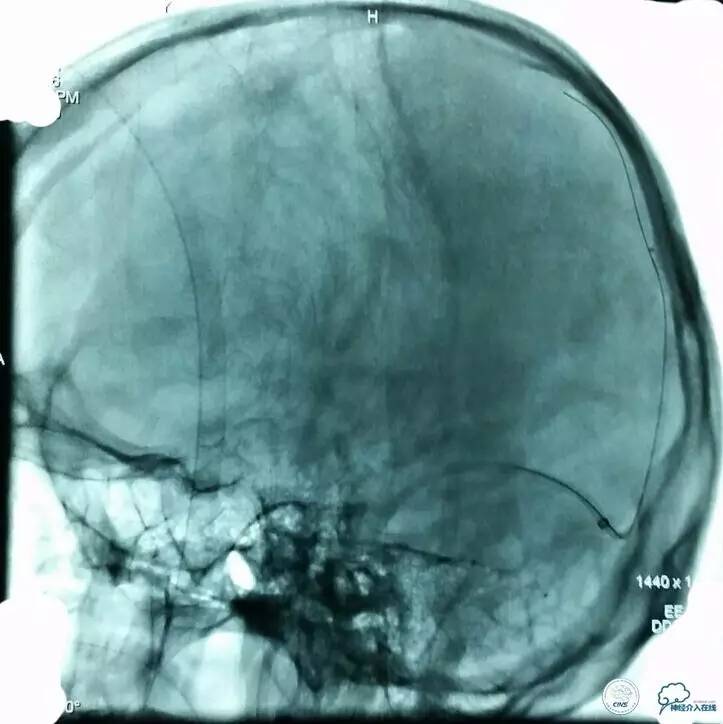

▼术前造影和MRV一致: